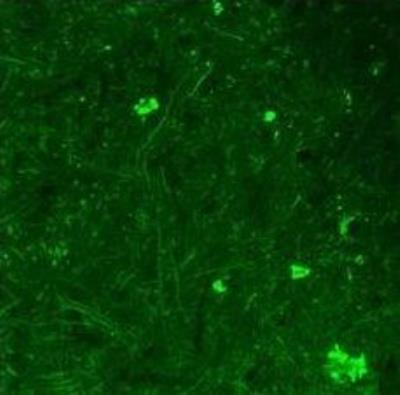

Supportive validation

- Submitted by

- Novus Biologicals (provider)

- Main image

- Experimental details

- Immunohistochemistry: BDNF Antibody [NBP1-59304] - Ventral horn region of mouse spinal cord. Concentration 1:200